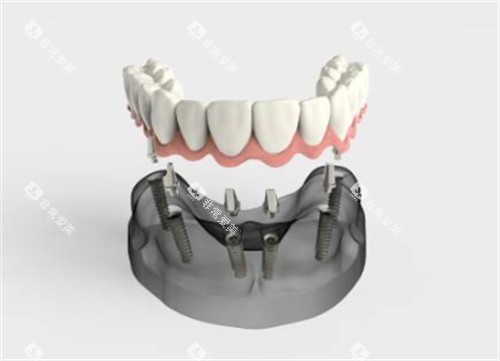

种植牙